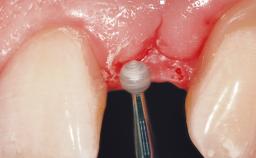

Immediate Placement of an Implant in a Maxillary Right Central Incisor Site

A 30-year-old female patient was referred to the office for the treatment of tooth 11. Her chief concern at the initial visit was to inquire, “Why is my tooth pink?” Upon clinical examination, it was determined that tooth 11 had a previous history of trauma and that the clinical crown had become noticeably pink in color as a result of internal resorption. This diagnosis was confirmed radiographically, indicating a large radiolucency involving the central and distal portions of the clinical crown. It was determined that restoration of this tooth was not possible, and that extraction was indicated. The presence of a mid-line diastema, which the patient wanted to reproduce, directed the treatment plan for tooth replacement utilizing a dental implant.

| Placement Protocol | Immediate implant placement |

| Tooth Site | Maxillary incisor or canine |

| Socket Morphology | Single-root socket |